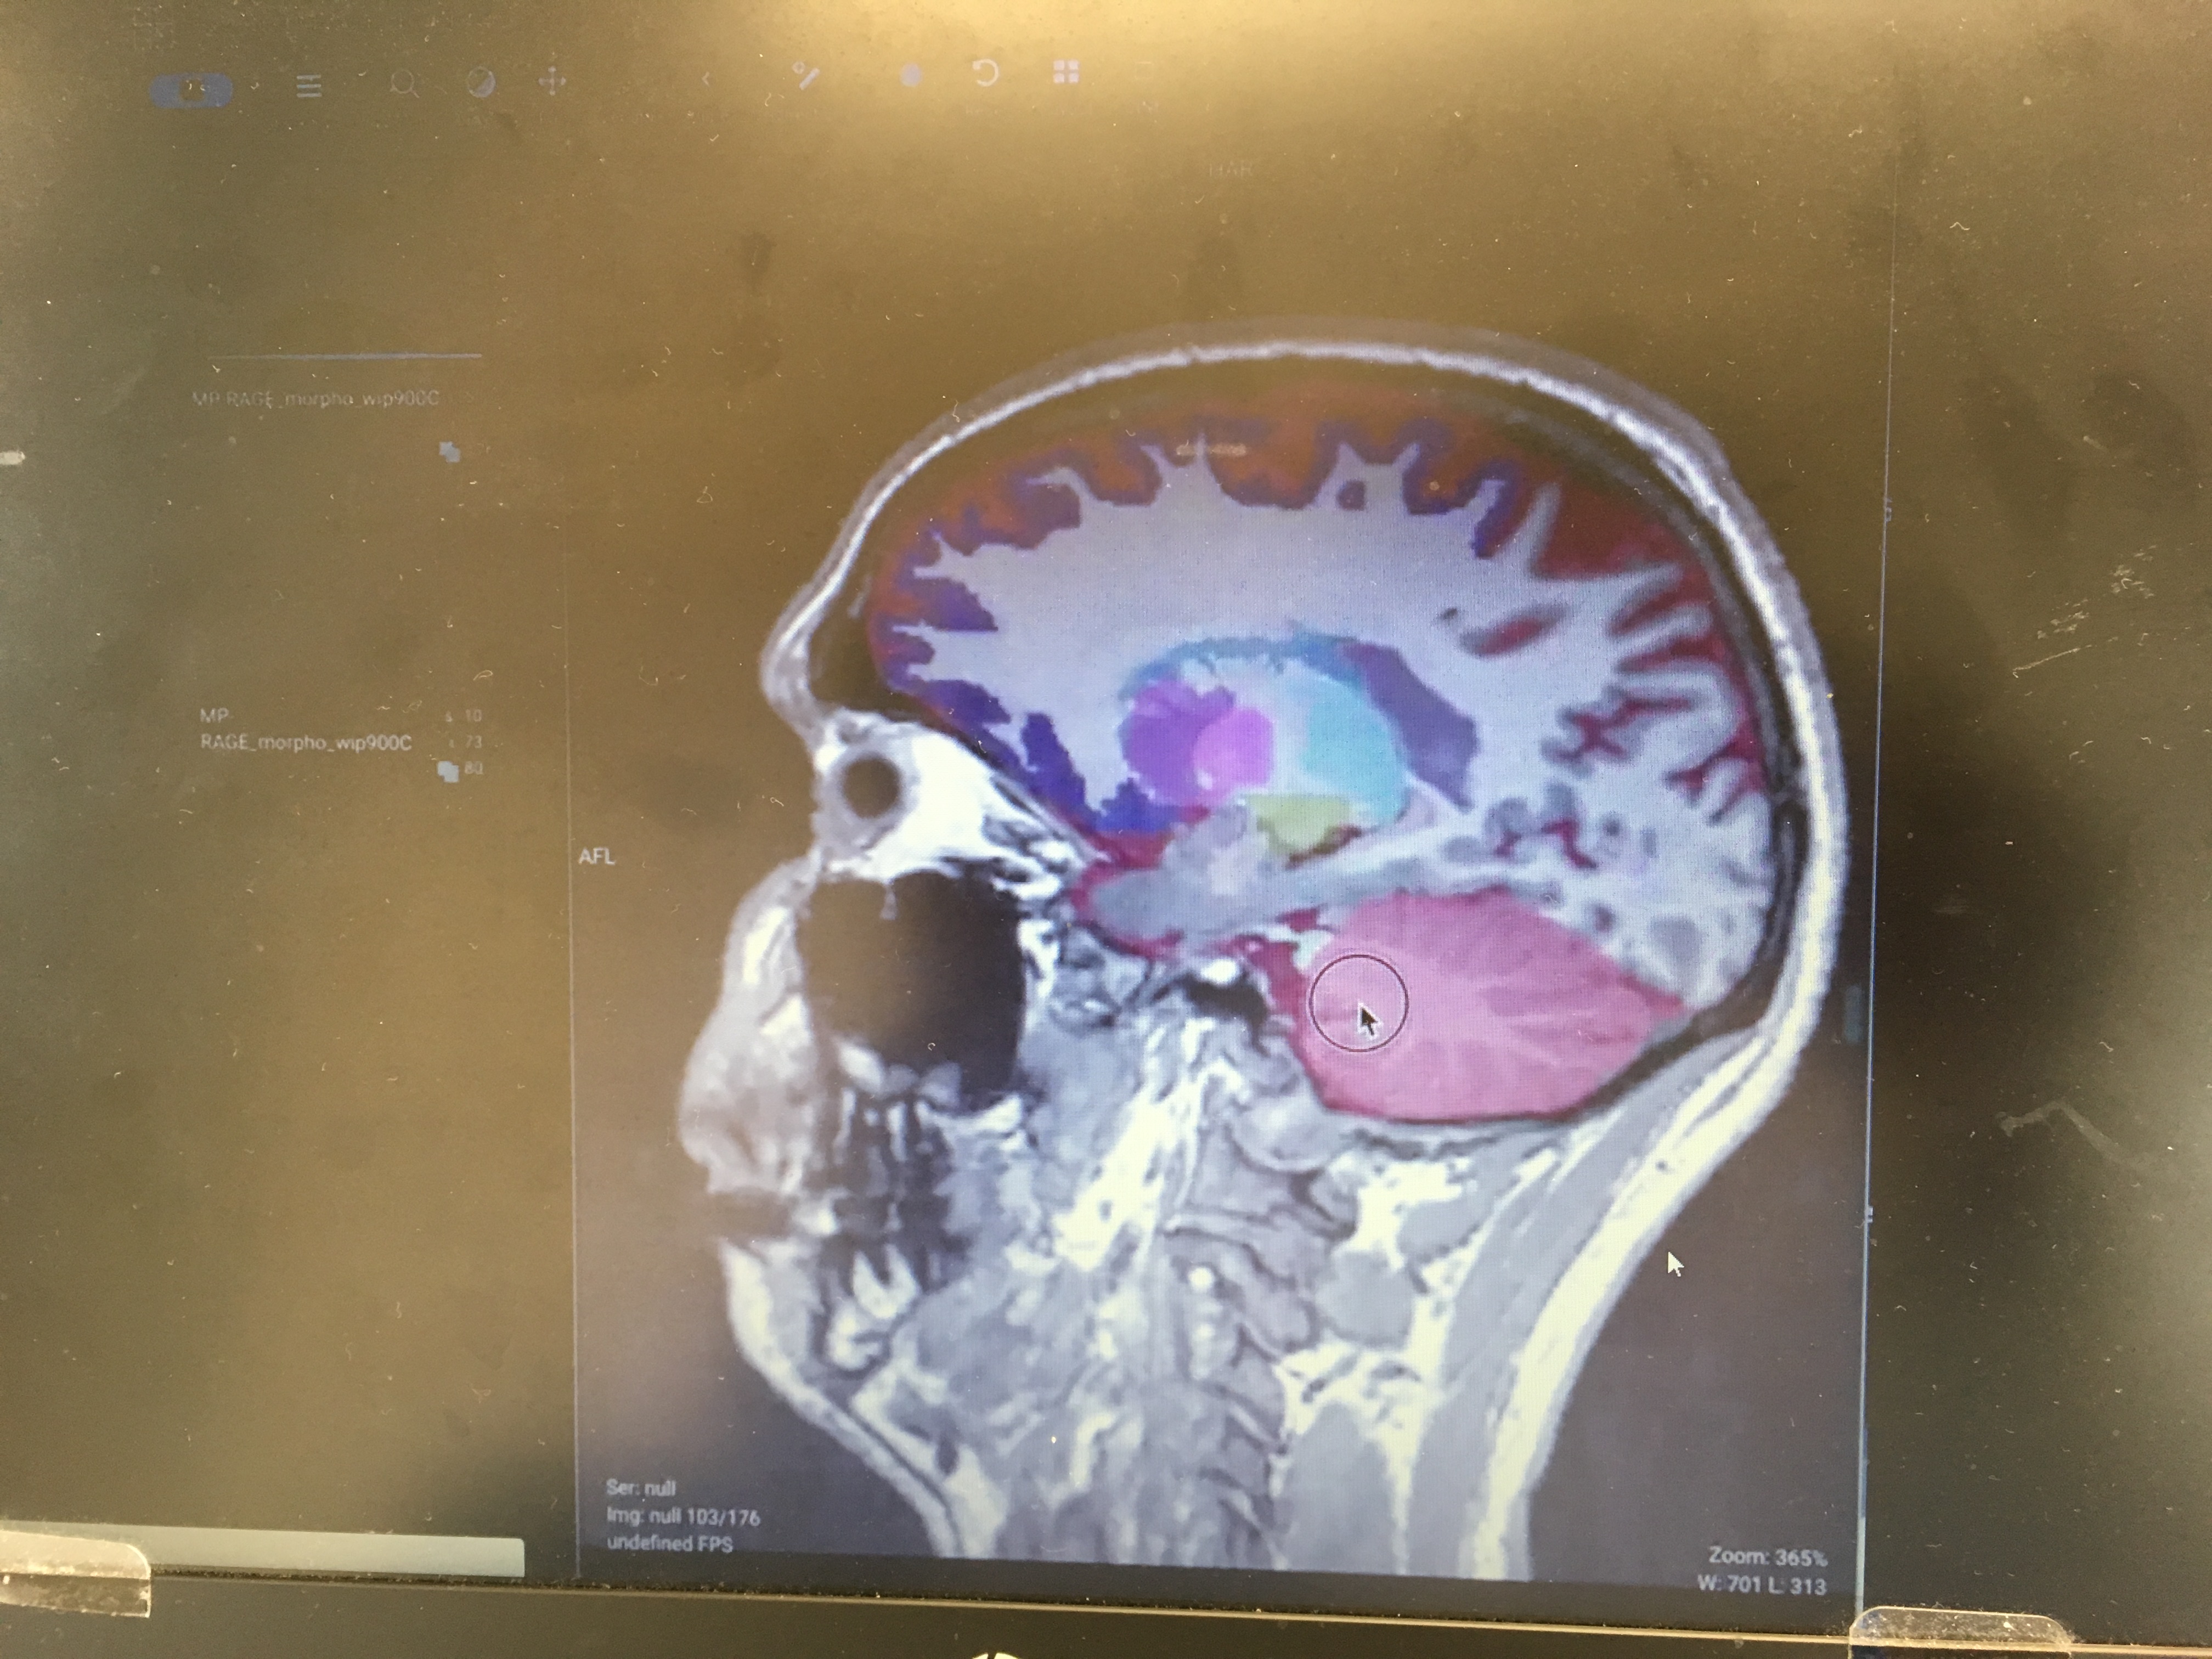

Brain Morphometry

Snapshot